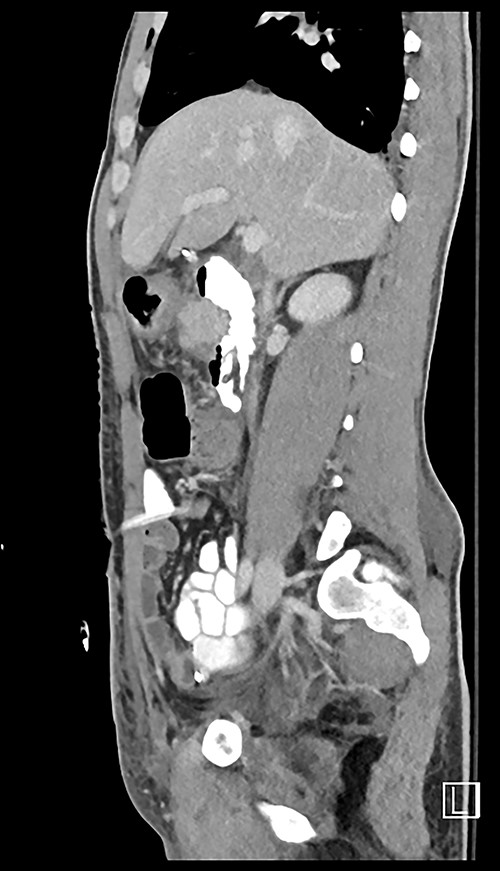

Here, we report a case of a 21-year-old man who was admitted to our hospital following a motor vehicle collision where he was a pedestrian, hit by a car and pushed against the bumper of another car. Upon arrival to the hospital, he was conscious and oriented, with normal vital signs. Abdominal examination revealed ecchymosis over the epigastric area with tenderness, however, no distention was noticed. Focused assessment with sonography for trauma result was positive in the right upper quadrant. His initial blood test results revealed a white blood cell (WBC) count of 26.5 × 109 cells/l and a hemoglobin level of 150 g/l. His serum amylase and lactic acid levels were 92 U/l and 4.53 mmol/l, respectively. His base deficit was 4.3. He underwent abdominal computed tomography (CT) with oral contrast, which showed query duodenal and possible pancreatic transection with active arterial extravasation (Figs 1–3). In addition, CT revealed a comminuted right intertrochanteric femoral fracture without associated vascular injury.

Exploratory laparotomy was performed, which revealed ~500 ml of blood in the peritoneal cavity, central retroperitoneal hematoma, peripancreatic hematoma and complete transection of the third part of the duodenum. The retroperitoneal hematoma and peripancreatic hematoma were nonexpanding. A formal end-to-end anastomosis of the third part of the duodenum was performed using 3–0 polydioxanone (PDS) in a single layer. Double decompression of the duodenum was achieved using a nasoduodenal tube (ND) and a retrograde duodenostomy tube. A jejunostomy tube was created for feeding as well.

Despite its limitations in distinguishing between duodenal hematoma and duodenal perforation, CT with intravenous and intraluminal contrast remains the gold standard diagnostic test in stable patients with blunt abdominal trauma [1]. In the reported case, CT revealed duodenal and possible pancreatic transection with active arterial extravasation.